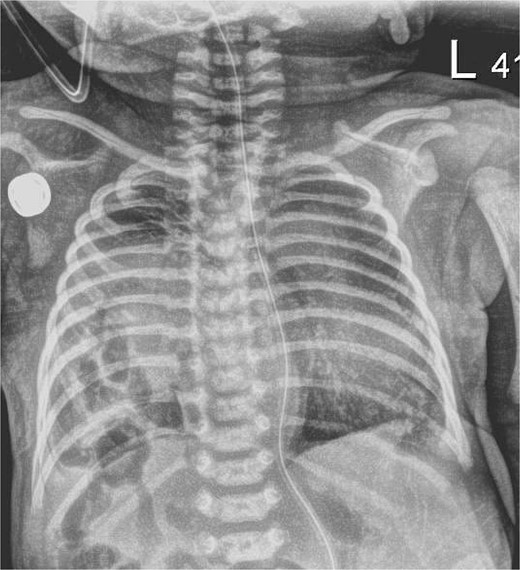

The infant presented with respiratory distress within one hour of life and underwent intubation. A chest X-ray showed a right sided CDH with bowel in the right chest and no evidence of mediastinal shift (Fig. 1). An echocardiogram showed mild dilation of the right atrium and right ventricle with moderately increased pulmonary artery pressures with a large PDA and PFO without flow reversal or left to right shunting. The initial echo showed three pulmonary veins with two left sided veins draining into the left atrium and a right upper pulmonary vein draining into the left atrium.

Chest X-ray, hour of life 1: there is a lucency in the right chest from the congenital diaphragmatic hernia as well as loops of bowel. There is no evidence of mediastinal shift and the superior aspect of the lung appears to aerate.